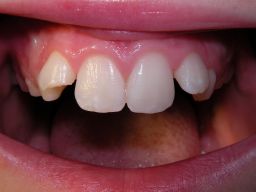

| Hier ein weiterer Fall, ein junges Mädchen nach einem Schulunfall: | |||||||||||||||||||||||||||||||||||||||||||||||||||||||||||||||||||||||||

![]() | Das Kind kam nach dem Unfall in die Praxis. Der Zahn war heiß-/kaltempfindlich und wurde erst einmal über ein paar Wochen mit einem provisorischen Zement versorgt. Die Beschwerden klangen ab, dann erfolgte die endgültige Füllung (ohne Zuzahlung), siehe rechts. Eine langfristige Alternative wäre hier eine keramische Verblendschale (Veneer), aber dafür ist das Kind aktuell zu jung. |

![]() | |||||||||||||||||||||||||||||||||||||||||||||||||||||||||||||||||||||||